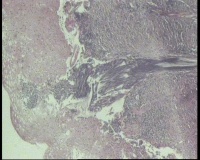

镜下见鳞状上皮大部分如(图1) ,仅局灶鳞状上皮异型(图2-4),细胞似牵拉变形,部分腺腔内见异型细胞团,这些细胞跟LEEP刀手术电凝有关系吗?这个怎么报?累腺明显,上皮图1怎么报?能报CINII—III累及腺体吗?还是宫颈高级别鳞状上皮内病变累及腺体

图1

CIN2-3累腺,有机械损伤,要按1-12点分别报告,要报告内外切缘情况。